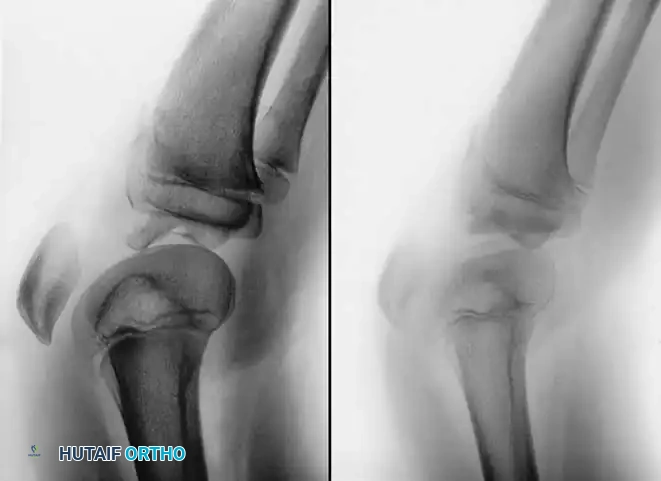

Radiographically, this injury is notoriously deceptive. Because the avulsed fragment is predominantly unossified cartilage, the standard lateral radiograph may only reveal a minute "fleck" of bone. This falsely benign appearance frequently leads to missed diagnoses.

Surgical Warning: When a pediatric patient presents with an inability to perform a straight leg raise, a palpable infrapatellar defect, and a high-riding patella, a sleeve fracture must be assumed regardless of how benign the radiograph appears. Magnetic Resonance Imaging (MRI) is the gold standard for delineating the true extent of the cartilaginous avulsion.